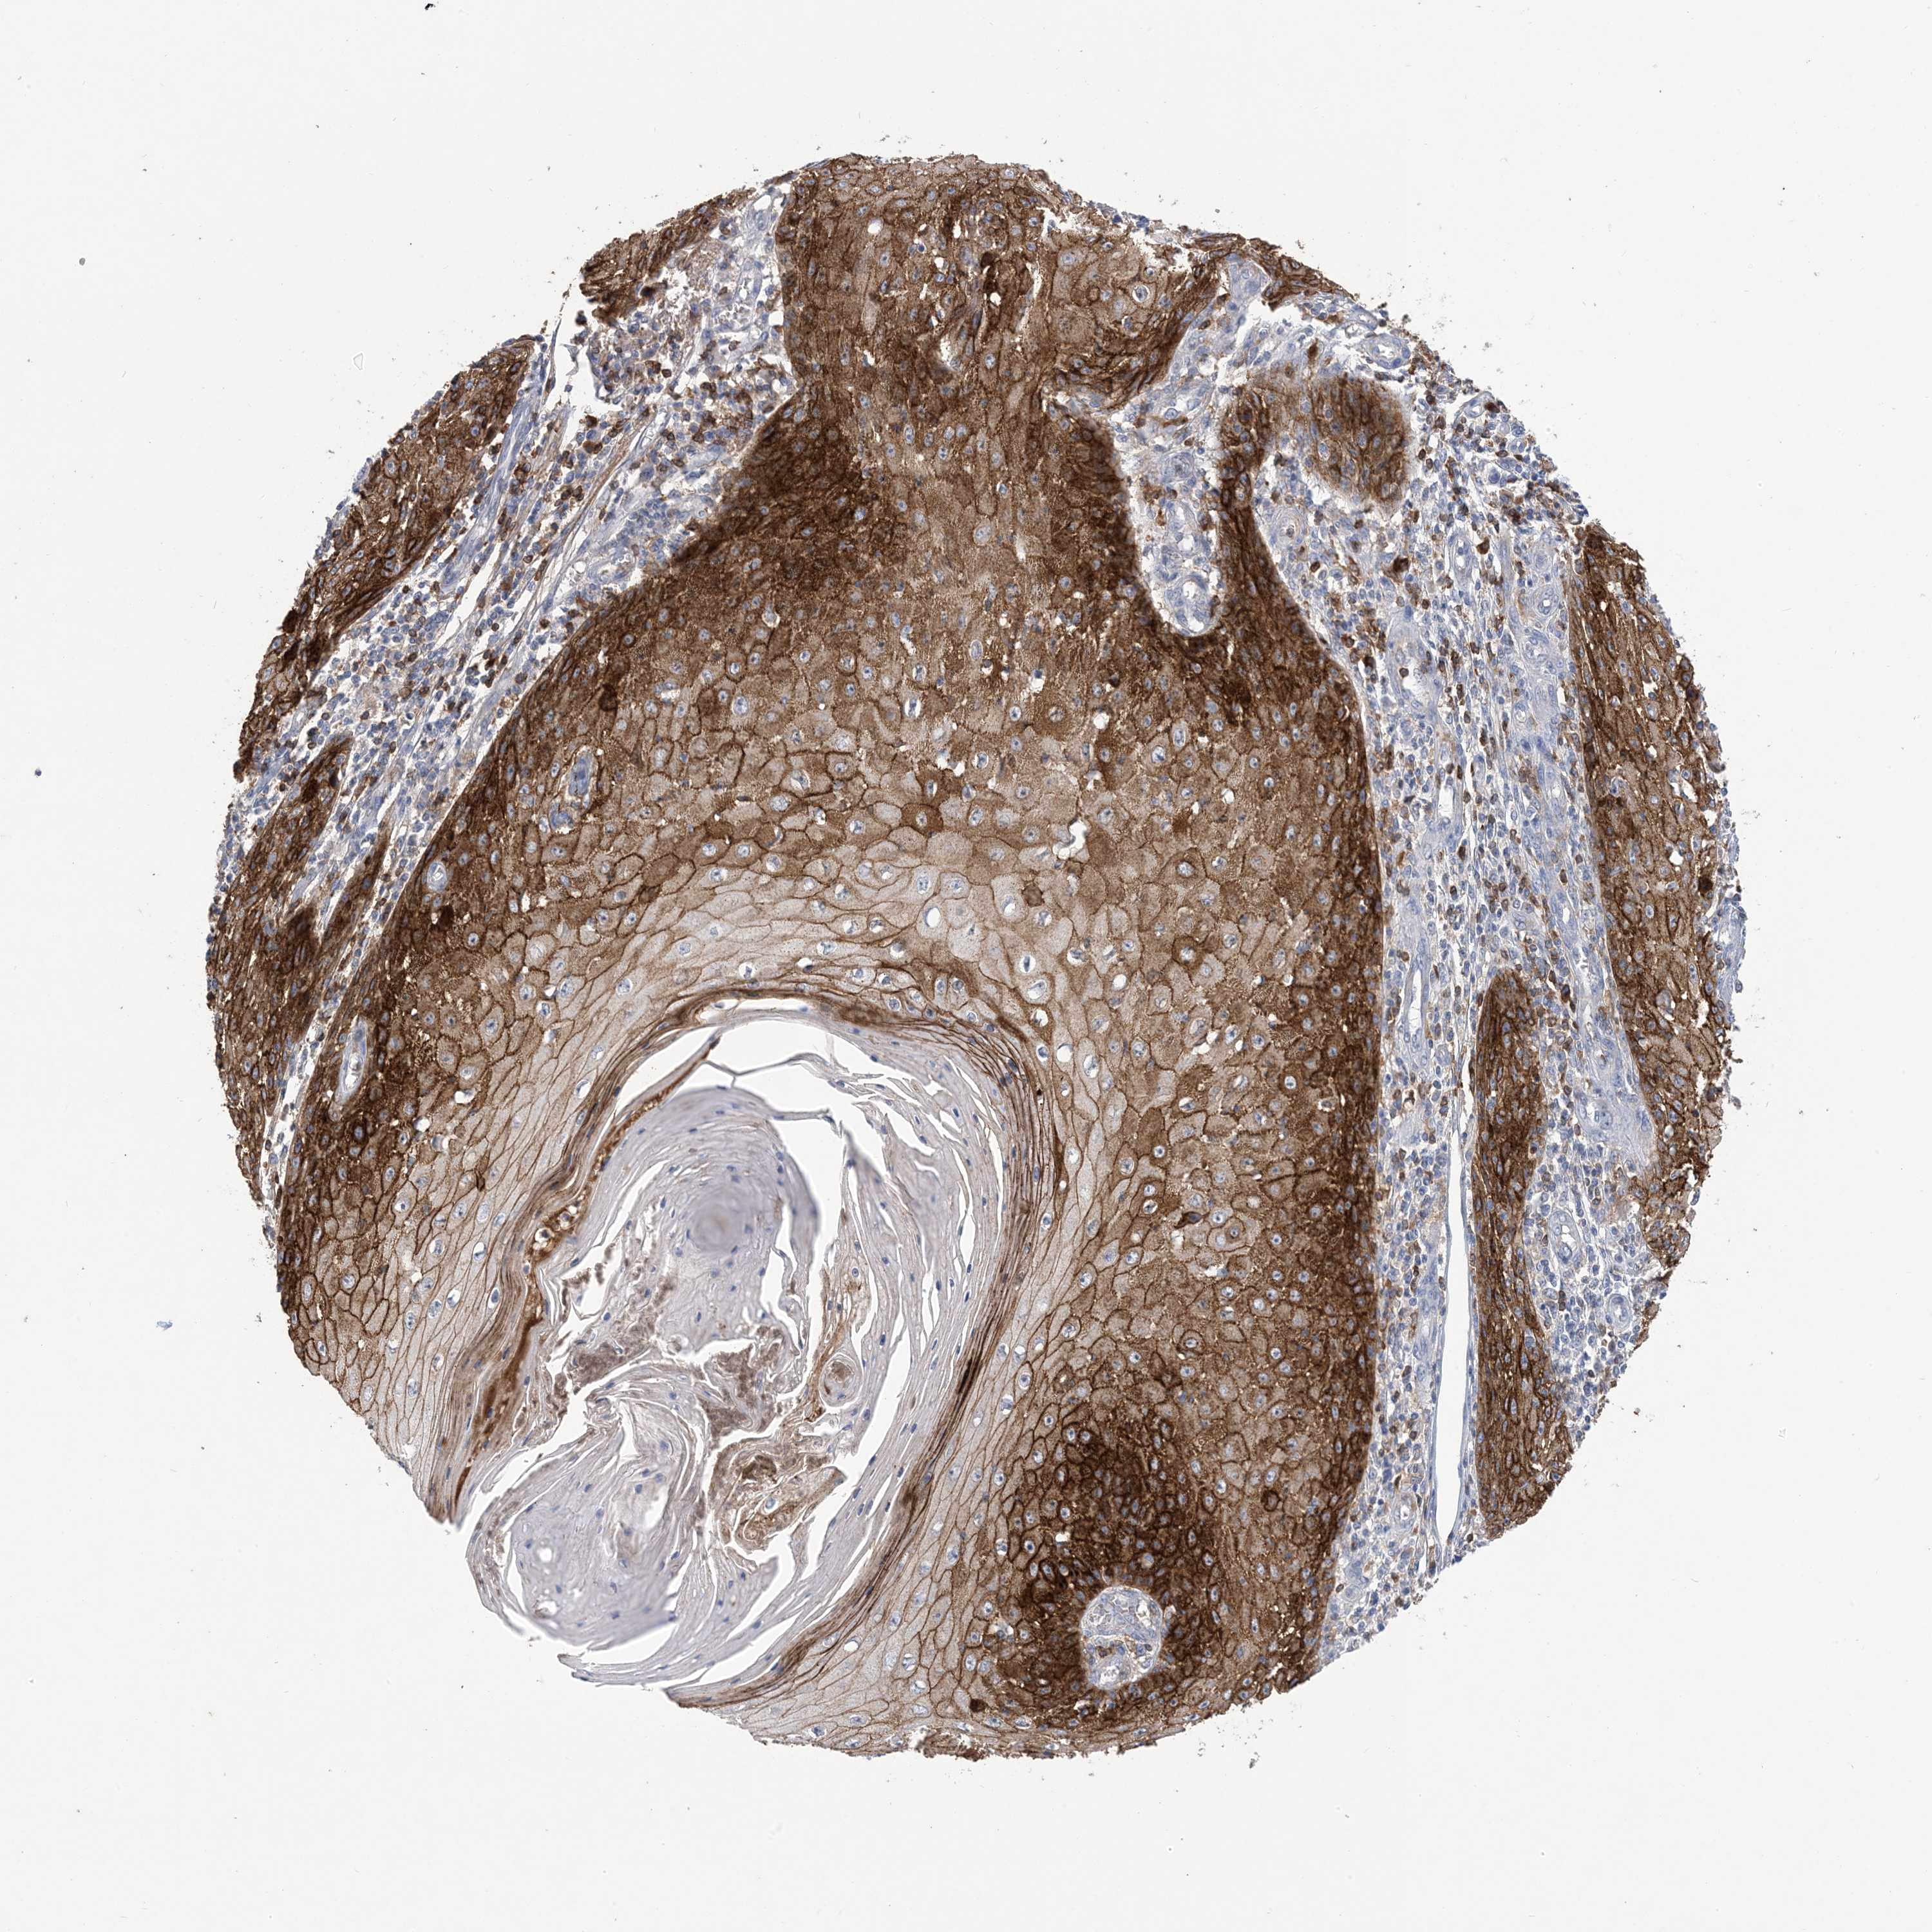

Basal cell and squamous cell cancer

SKIN CANCER - Protein expressioni

A mouse-over function shows sample information and annotation data. Click on an image to view it in a full screen mode. Samples can be filtered based on level of antibody staining by selecting one or several of the following categories: high, medium, low and not detected. The assay and annotation is described here.

Each image is clickable and will lead to virtual microscopy that enables deeper exploration of all samples and also displays staining intensity scores, fraction scores and subcellular localization as well as patient and tissue information for each sample.

Antibody HPA049265

Squamous cell carcinoma, NOS